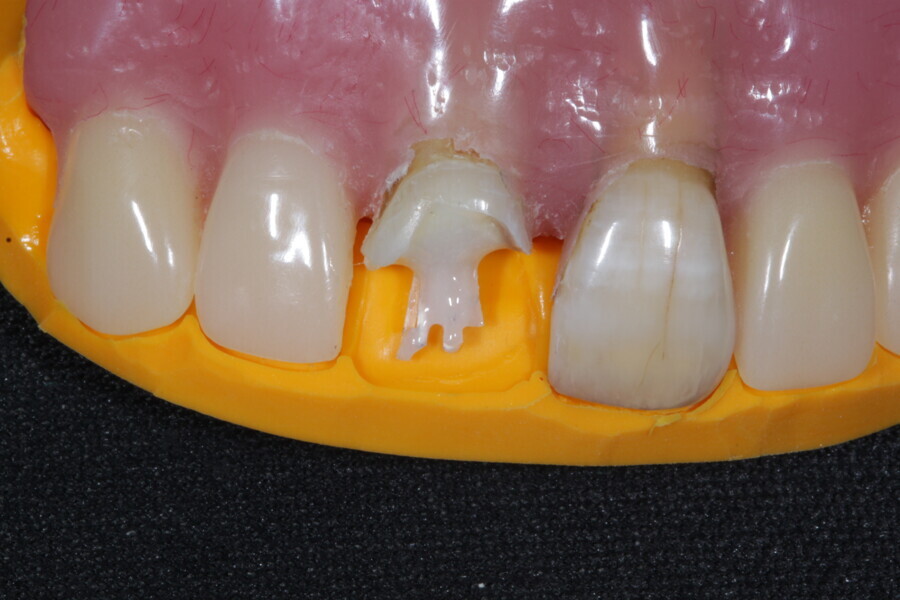

1. functional and aesthetic reconstruction of a maxillary anterior tooth using fibre-reinforced flexible micro-posts after endodontic treatment (Figs. 3–20);

Example 1—showing functional and aesthetic reconstruction of a maxillary anterior tooth using fibre-reinforced flexible micro-posts after endodontic treatment.